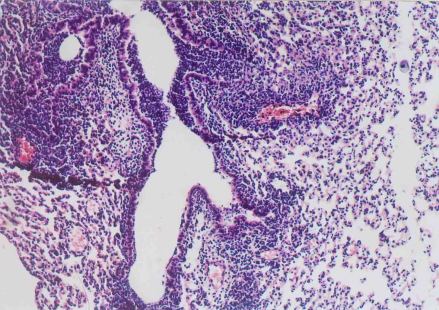

当机体免疫力较强,病原菌数量较少,毒力较弱时,不出现明显病症,成为隐性感染;当病原菌与人体免疫力的互相作用保持平衡状态时,病原菌潜伏在病灶内,成为潜伏感染;当人体免疫力较弱,病原菌入侵数量多,毒力强时,则出现明显病症,成为显性感染。

支原体、衣原体感染人体后,首先侵入柱状上皮细胞并在细胞内生长繁殖,然后进入单核巨噬细胞系统的细胞内增殖。由于支原体、衣原体在细胞内繁殖,导致感染细胞死亡,同时尚能逃避宿主免疫防御功能,得到间歇性保护。支原体、衣原体的致病机理是抑制被感染细胞代谢,溶解破坏细胞并导致溶解酶释放,代谢产物的细胞毒作用,引起变态反应和自身免疫。

当人体感染支原体、衣原体后,产生特异性的免疫,但是这种免疫力较弱,持续时间短暂,因此,支原体、衣原体感染容易造成持续,反复感染,以及隐性感染。细胞免疫方面,大部分活动性已治愈的衣原体患者,给予相应的抗原皮内注射时,常引起迟发型变态反应。这种变态反应可用淋巴细胞进行被动转移。此种免疫性很可能是T细胞所介导。体液免疫方面,在支原体、衣原体感染后,在血清和局部分泌物中出现中和抗体。中和抗体可以阻止衣原体对宿主细胞的吸附,也能通过调理作用增强吞噬细胞的摄入。